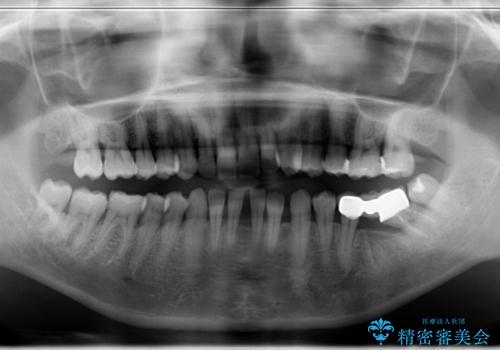

- 左下のブリッジの適合が悪く、虫歯になっていました。

左下6を抜いてからブリッジを入れるまでに放置してしまったために、左下7が前に倒れたこと、左下8も後ろから押す向きに生えていたこともあり、左下7がかぶせものを入れづらい状態になっていたためと考えられました。

また左下7は倒れていたため、清掃性が悪く近心のポケットは7mmありました。

そのため、左下8を抜いて、左下7を部分矯正で後ろに起こしてからブリッジを新製することとしました。